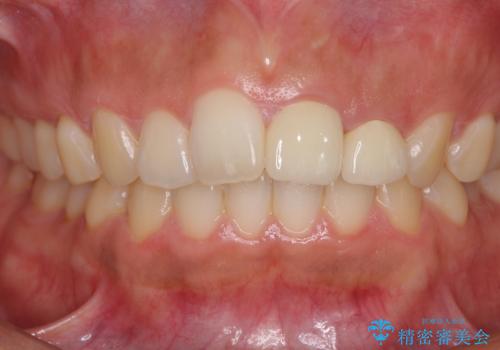

- 中学生の時にスポーツで折ってしまった前歯が変色してしまったとのことで来院された患者様です。

結婚式に向けてオールセラミッククラウンにて仕上げていくこととしました。

既にクラウンが装着されていた歯は歯根の先端に病変が認められたため、根管治療を行うこととしました。

仮歯装着の時点で自然な見た目となり、オールセラミッククラウンを装着した際には、まるで自分の歯のようと喜んでくださいました。